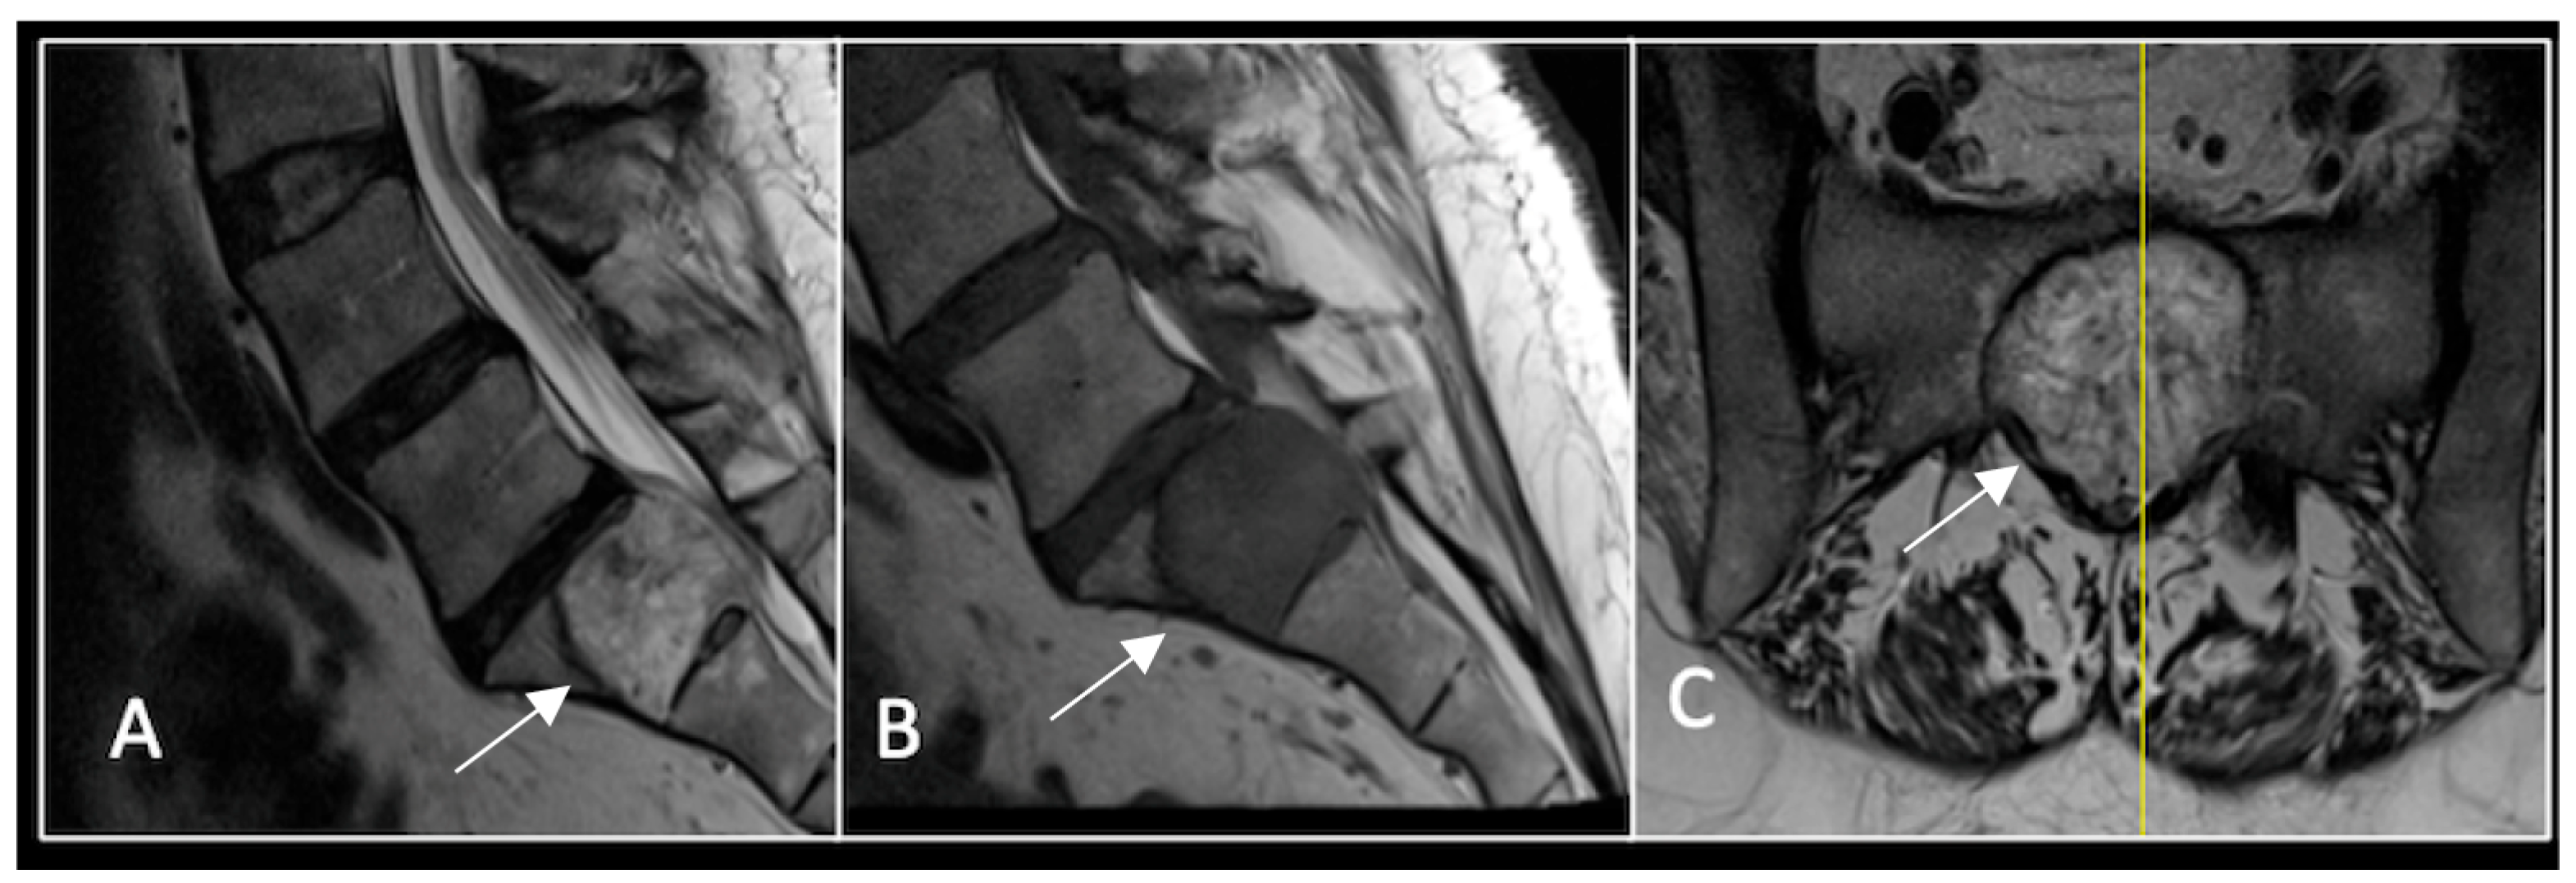

This 63-year-old male presented with sacral pain and right-sided S1 radiculopathy. He was subsequently referred to our institution after diagnostic imaging revealed a destructive lesion within the S1 vertebra (Figure 4). The patient developed symptoms of acute cauda equina syndrome, for which we recommended an emergent surgical decompression to be performed at the referring hospital. Biopsy confirmed a conventional chordoma. The patient chose to undergo separation surgery, given the significant morbidity associated with an en-bloc sacral resection, including sacrifice of the neural structures innervating his bladder and bowel. He received adjuvant proton beam therapy, and 6-monthly surveillance imaging revealed stable disease (Figure 5). Unfortunately, 12 months post-separation surgery, there was evidence of tumour progression with epidural extension and symptomatic deterioration in bladder function, requiring revision surgical debulking (Figure 6).

Figure 4.

MRI demonstrating a destructive lobular sacral mass (arrow) with invasion of the S1 vertebral body and complete compression of the cauda equina neural elements. The yellow line on the axial image represents the plane of the corresponding axial section. (A) T2W sagittal; (B) T1W sagittal; (C) T2W axial.